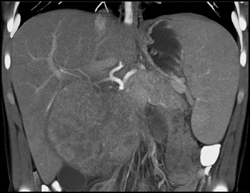

Hepatoma